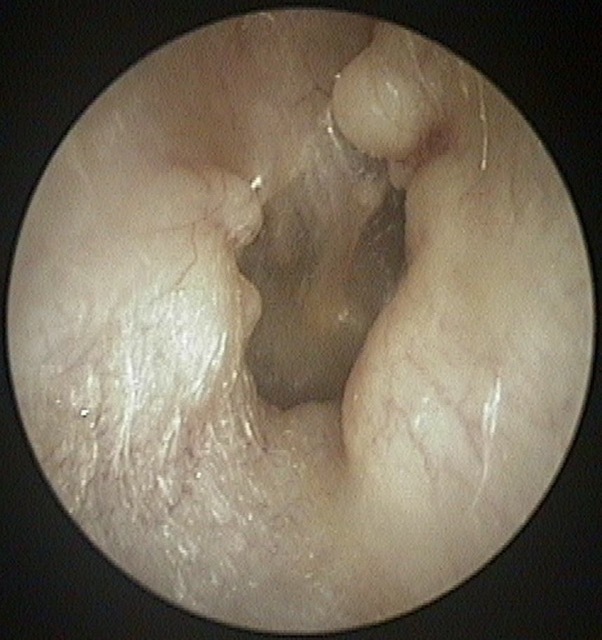

Atelectasis/Retraction

Cholesteatoma Clinical

Tympanic Membrane